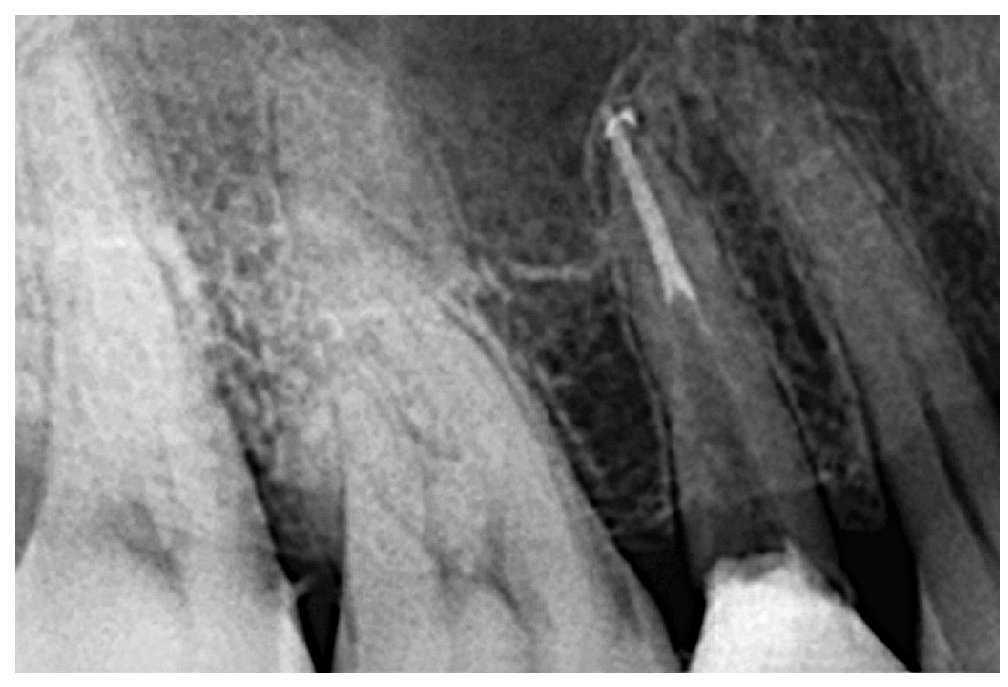

Una paciente de 32 años acude al centro para recibir un tratamiento endodóntico. La paciente refirió haber sufrido un cuadro de dolor dental agudo durante unas vacaciones en el extranjero, motivo por el que le fue practicada una apertura cameral del diente afectado. La paciente es alérgica a la penicilina. A la inspección, se observó una apertura cameral con obturación provisional del segundo premolar superior derecho. En la radiografía intraoral se apreciaba un conducto radicular instrumentado que guardaba una relación anatómica estrecha con el seno maxilar (fig. 1).

Figura 1. Hallazgos radiológicos iniciales.